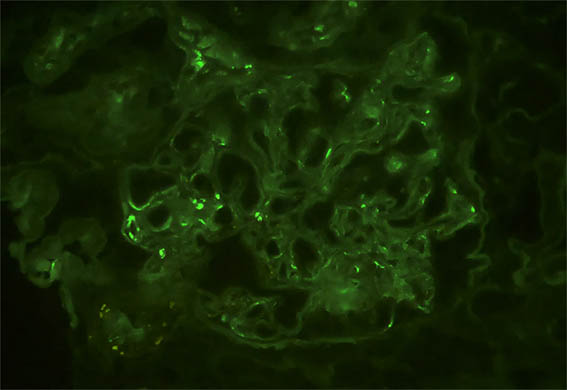

Figura 10. Inmunofluorescencia para IgA, X400. Positividad mesangial y subendotelial.

Figura 11. Inmunofluorescencia para IgM, X400. Positividad mesangial y subendotelial.

Figura 12. Inmunofluorescencia para C3, X400. Positividad mesangial y subendotelial.

Figura 13. Inmunofluorescencia para IgG, X400. Negativa (o trazas).

Inmunofluorescencia directa para C1q: Negativa; kappa y lambda: Tinción similar a la de IgA e IgM.